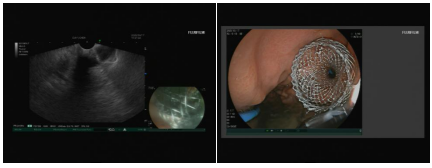

手术如期进行,由消化内科徐洪雨教授与李冬月副教授领衔的超声内镜团队主导手术,同时联合腔镜室全体护理人员及麻醉科团队开展紧密协作。手术中,团队通过线阵超声内镜的精准引导,成功为患者完成经胃壁LAMS对吻支架放置,胃肠吻合术顺利落地!术后,患者因十二指肠狭窄引发的梗阻问题得到了有效解决,恢复了正常进食饮水。